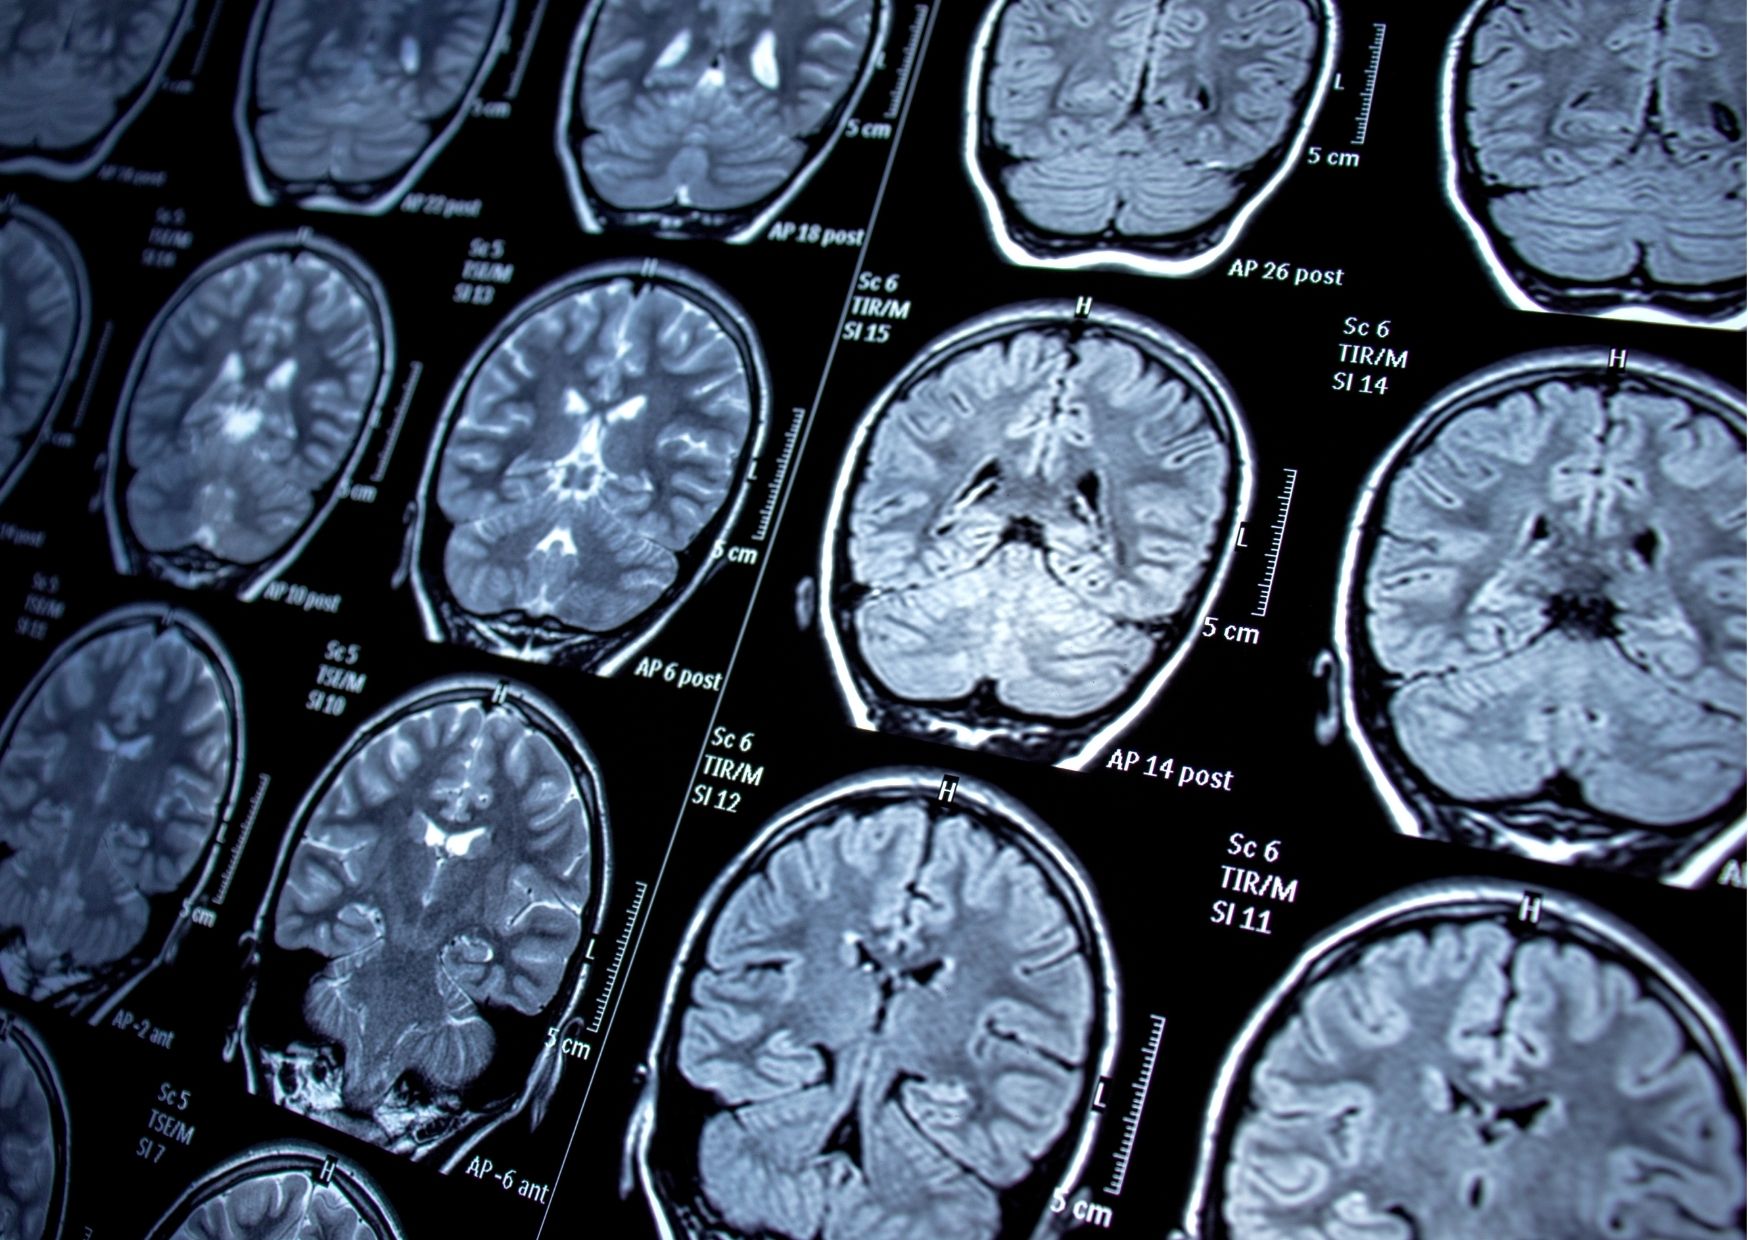

Pierwszym rodzajem badań na padaczkę badanie neurologiczne – pracy mózgu (EEG), budowy mózgu (np. tomograf), a także badania krwi. Badanie EEG (elektroencegalogiczne) pokazuje tzw. fale mózgowe, czyli czynność bioelektryczną mózgu – jest to badanie nieinwazyjne i bezbolesne. Wynik takiego badania można na bieżąco obserwować na ekranie monitora. Należy jednak pamiętać, że nie zawsze w przypadku padaczki, badanie EEG musi dać nieprawidłowy wynik. Nieprawidłowy wynik badania EEG nie przesądza także o występowaniu padaczki u pacjenta.

Czy jeżeli wynik EEG/rezonansu/tomografu jest prawidłowy jest sens wykonywać badania genetyczne?

Zdecydowanie tak. W wielu przypadkach w przebiegu padaczki nie występują niepokojące zmiany w zapisie EEG lub w badaniach obrazowych. Może to oznaczać wykluczenie widocznych, mechanicznych uszkodzeń mózgu. Jest to tym bardziej wskazanie, aby wykonać diagnostykę genetyczną i sprawdzić przyczyny napadów, których nie widać w badaniach obrazowych.